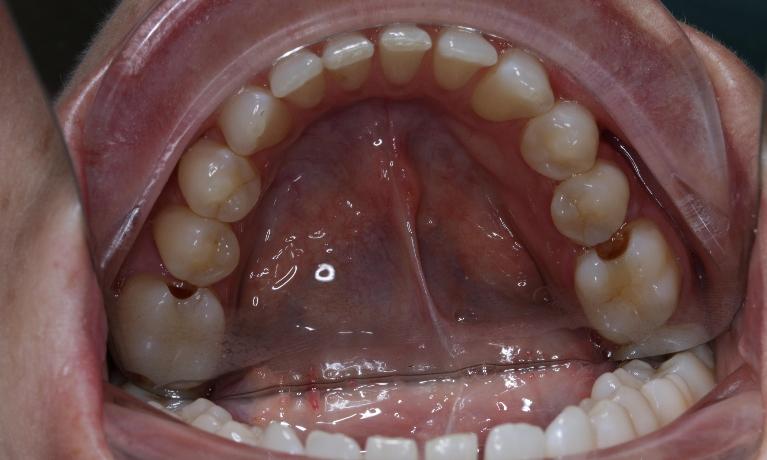

If you need a filling but don’t want it to be visible, tooth-coloured composite fillings can be an appealing alternative. Composites can also be used for minor reshaping of chipped teeth or to fill small gaps between teeth to give you a more even, appealing smile.

Composite fillings are usually formed using a mixture of resins, fillers, and colourants, and applied to the tooth in layers and “cured". Unlike silver amalgam fillings, composites can be made to match the colour of your natural teeth.

Composite fillings offer a better aesthetic than metal fillings. They can also act more like natural tooth structure, helping to avoid fractures due to uneven stress when biting.